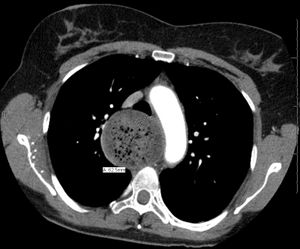

말기 식도이완불능증은 심하게 확장되고 뒤틀린 식도를 특징으로 한다.[12] 이전에 치료를 받았음에도 불구하고 증상이 재발하고 영양 상태가 악화된 환자에게는 식도절제술이 필요할 수 있다.[13][14][15]